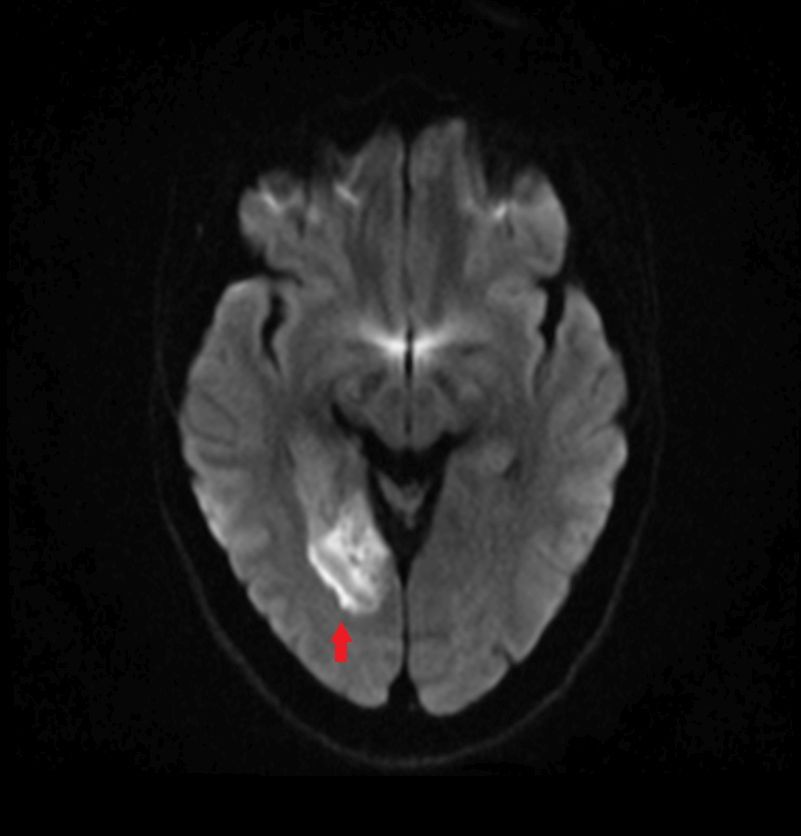

Die diffusionsgewichtete Magnetresonanztomographie (DW-MRT) ist eine spezielle Form der MRT, die die Bewegung von Wassermolekülen im Gewebe sichtbar macht. Dazu wird die Diffusion von Wasserstoffprotonen in verschiedenen Geweben gemessen. Die DW-MRT ist nützlich für die Diagnose von Erkrankungen, die die Diffusion von Wasser im Gewebe beeinträchtigen (Diffusionsrestriktion), wie z.B. akute Schlaganfälle, manche Tumore oder einige Formen von Entzündungen. Die DW-MRT kann auch Informationen über die Struktur und Organisation von Nervenfasern liefern, indem sie die Richtung der Diffusion misst. Dies wird als Diffusionstensorbildgebung (DTI) bezeichnet.

Dieser Vorgang wird für mehrere Richtungen des Diffusionsgradienten wiederholt, um die Diffusion in verschiedenen Raumrichtungen zu erfassen. Die resultierenden Bilder werden als diffusionsgewichtete Bilder bezeichnet und können zur Berechnung von Parametern wie dem Apparent Diffusion Coefficient (ADC) verwendet werden, der als

ADC-Karte dargestellt wird.

diffusionsgewichetes Bild bei Infarkt

gleicher Patient mit ADC-Karte